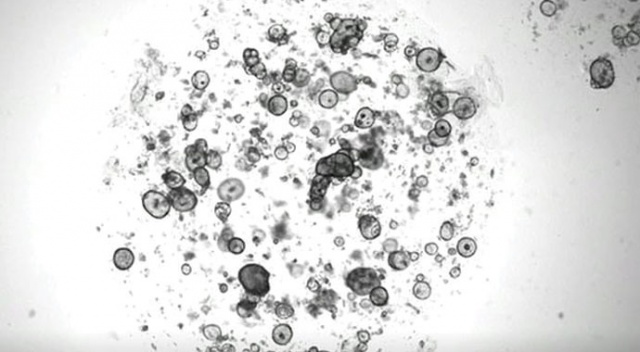

Hollandalı bilim adamları laboratuvar ortamında gözyaşı bezi geliştirdi. Göz yuvarlağının üst kısmında bulunan gözyaşı bezi, su, proteinler, lipitler ve elektrolitler ihtiva eden gözyaşı salgılıyor. Bunun düzgün çalışmaması göz kuruluğu, kornea ülseri ve hatta ileri vakalarda körlüğe yol açabiliyor. Bilim adamları, geliştirdikleri bezin bu tür durumlarda hastalara nakledilmesini planlıyor. Merkezi Utrecht’te bulunan Hubrecht Institute kurumundaki araştırmaya liderlik eden biyolog Yorick Post, “Yetişkinlerin en az yüzde 5’inde göz kuruluğu rahatsızlığı var. Ancak tedavi seçenekleri sınırlı çünkü gözyaşı bezini incelemek için güvenilir, laboratuvar ortamında uzun vadeli modeller yok. Çalışmalarımız, naklin dışında bezin çalışma sisteminin daha iyi anlaşılmasına da yol açacaktır” dedi. Araştırmacılar, uzun çabalar sonrasında, insanlarda gözyaşı salgılanmasını tetikleyen 'noradrenalin' uygulayarak gözyaşı bezinden sıvı akmasını başardı.